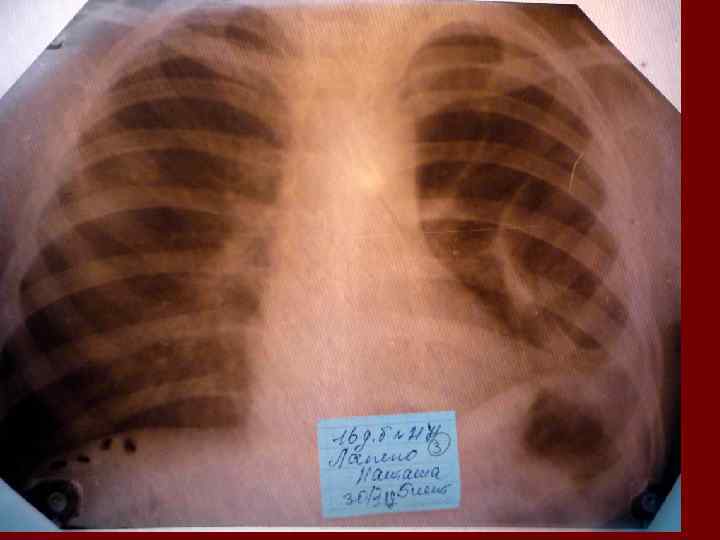

Пневмония Воспалительный процесс в респираторных отделах легкого с наличием внутриальвеолярной экссудации. n Это острое инфекционное заболевание легочной паренхимы, диагностируемое по синдрому дыхательных расстройств и/или физикальным данным при наличии очаговых или инфильтративных изменений на рентгенограмме. n Пневмония – это, прежде всего, клинический диагноз, который ставит врач у постели больного, и только затем подтверждает рентгенологически. n

Пневмония - это неспецифическое воспаление легочной ткани, в основе которого лежат инфекционный токсикоз, дыхательная недостаточность, водно – электролитные и прочие метаболические нарушение с патологическими изменениями во всех органах и системах детского организма. Заболевание диагностируется на основании синдрома дыхательных расстройств и/или физикальных данных и верифицируется рентгенологически выявлением инфильтративных изменений в легких.

Показания к назначению рентгенологического исследования: - лихорадка в течение 3 и более дней при наличии кашля; - одышка; - цианоз; - выраженные симптомы интоксикации; - типичные аускультативные или перкуторные изменения ( особенно асимметричной локализации).

Долевая пневмония характеризуется лобарным пневмоническим инфильтратом. Крупозная ( пневмококковая) пневмония диагностируется прежде всего по клиническим данным. Крупозная пневмония сохраняет свою типичную картину пневмококковой пневмонии: острое начало с характерными клиническими данными, циклическое течение, несклонность к деструкции, гомогенной и лобарной инфильтративной тенью при рентгенологическом исследовании. Вместе с тем, широкое использование антибиотиков способствовало значительному снижению числа крупозных пневмоний у детей. Интерстициальная – редкая форма пневмоний, при которой оказывается поражен прежде всего интерстиций. Как правило, интерстициальная пневмония обусловлена вирусами, пневмоцистами, внутриклеточными микроорганизмами и грибами.

Морфологическую форму пневмонии определяют по клинико – рентгенологическим данным: выделяют очаговую, очагово – сливную, долевую ( крупозную), сегментарную и интерстициальную пневмонии. Очаговая – наиболее распространенная форма. Пневмонические очаги чаще бывают размером 1 см и более. Очагово – сливная – инфильтративные изменения в нескольких сегментах или во всей доле легкого, на фоне которых могут быть видны более плотные участки инфильтрации и/или полости деструкции. Сегментарная – в процесс вовлекается весь сегмент, который, как правило, находится в состоянии гиповентиляции, ателектаза. Морфологическая картина воспаления при очаговых и сегментарных пневмониях связана с первичным инфекционным воспалением в бронхах, что дает основание отнести эти варианты поражения легочной ткани к бронхопневмониям, нередко сопровождающихся бронхообструктивным или бронхообтурационным синдромами. В настоящее время данный тип пневмоний у детей встречается наиболее часто.